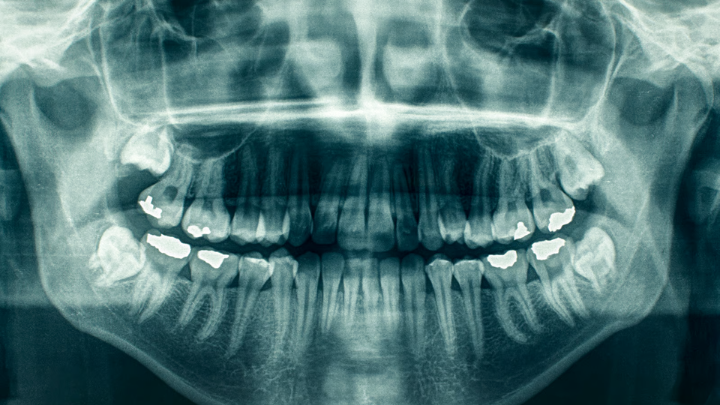

Os dentes vão além da função mastigatória e da estética. Cada estrutura dentária registra, ao longo do tempo, informações valiosas sobre o indivíduo. Para a odontologia, especialmente em áreas como a Odontologia Forense, a cavidade oral funciona como um verdadeiro arquivo biológico, capaz de revelar idade, padrões de comportamento e sinais de condições sistêmicas.

A estimativa de idade é uma das aplicações mais conhecidas da análise dentária. Em crianças e adolescentes, a sequência de erupção dos dentes permite avaliações bastante precisas. Já em adultos, o desgaste do esmalte, a retração gengival e a deposição de dentina secundária ajudam a indicar o avanço da idade.

Métodos mais recentes também analisam características microscópicas dos tecidos dentais, ampliando a precisão dessas estimativas e reforçando a ideia de que o envelhecimento deixa marcas mensuráveis na arcada.

A prática clínica envolve não apenas a execução de procedimentos, mas também a interpretação de sinais. A análise detalhada da arcada dentária, aliada à anamnese, permite identificar padrões e levantar hipóteses sobre o histórico e os hábitos do paciente.

Em campos como a Odontologia Legal, essa capacidade ganha ainda mais relevância, sendo utilizada na identificação de indivíduos e na análise de evidências em contextos investigativos.